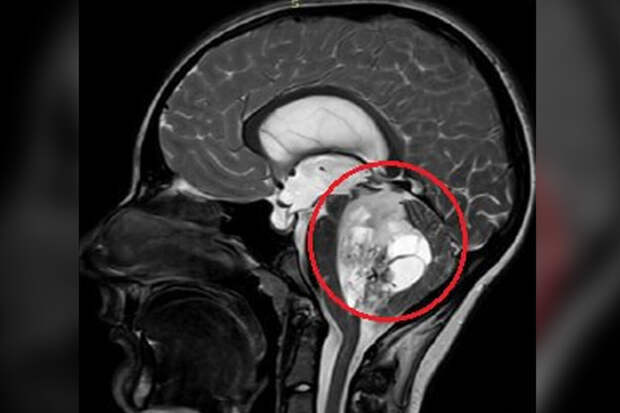

По словам медиков, юноша жаловался на постоянную тошноту и рвоту, которые не удавалось купировать консервативными методами. На обследовании специалисты обнаружили пятисантиметровую опухоль в задней черепной ямке.

По словам врачей, ее дальнейший рост мог привести к нарушению жизненно важных функций мальчика."Сложность данного случая заключалась в том, что опухоль росла из области, которая отвечает за жизненно важные функции - любое, даже маленькое повреждение могли привести к тяжелым неврологическим осложнениям", - отметили нейрохирурги.